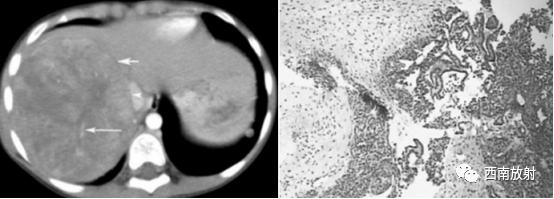

▲病例4:胎儿型肝母细胞瘤:男,9个月,肝右叶肝母细胞瘤,CT增强扫描示肿 瘤与周围正常肝组织边界清楚,似有假包膜 (短箭头),其内有裂隙状低密度区,瘤内可见较多粗细不一的肿瘤血管 (长箭头),下腔静脉主要为受压改变 (箭头 )。病理为肝母细胞瘤,胎儿型。

HE染色,低倍 40.肿瘤细胞排列成不规则梁索状,瘤细胞呈小圆形,胞浆丰富,部分透亮,胞核圆形或卵圆形,单个核仁,核分裂少见。肿瘤细胞间质血窦丰富,可有髓外造血灶瘤。另外见凝固性坏死,穿剌组织中未见间叶分化的成份,符合肝母细胞瘤,胎儿型。